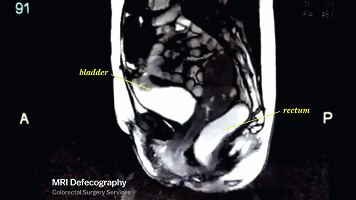

膀胱和直肠也会因为肌肉

的收缩反应开始颤抖

这也是为什么啪啪啪有时候会使你

出现尿急感的原因